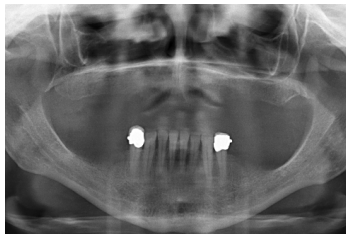

Para iniciar la fase de diagnóstico se realiza una radiografía panorámica que nos de una idea del estado general de ambos maxilares para iniciar el plan de tratamiento. En ella se ve como existe aparentemente altura en el reborde maxilar tanto a nivel anterior como posterior y un nervio dentario bajo en la mandíbula que nos permite tener una mayor cresta ósea residual disponible para la inserción de los implantes (Figura 3).